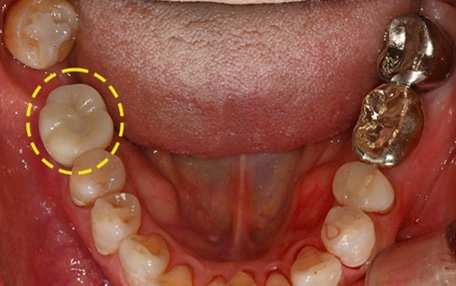

How is the treatment carried out?

At your first visit,

we check the overall condition using a panoramic X-ray and, if needed, a 3D CT scan,

including the position of the sinus, the height and thickness of the bone, and the location of the nerves.

Based on this diagnosis,

we determine whether the implant can be placed right away

or whether it would be better to proceed together with a sinus lift,

and we create a treatment plan tailored to each person’s condition.

Depending on the situation,

implant placement and the sinus lift may be performed on the same day,

or they may be carried out in stages after the bone has had enough time to settle.

The important thing is not to force it,

but to design the treatment flow so that each step progresses naturally.